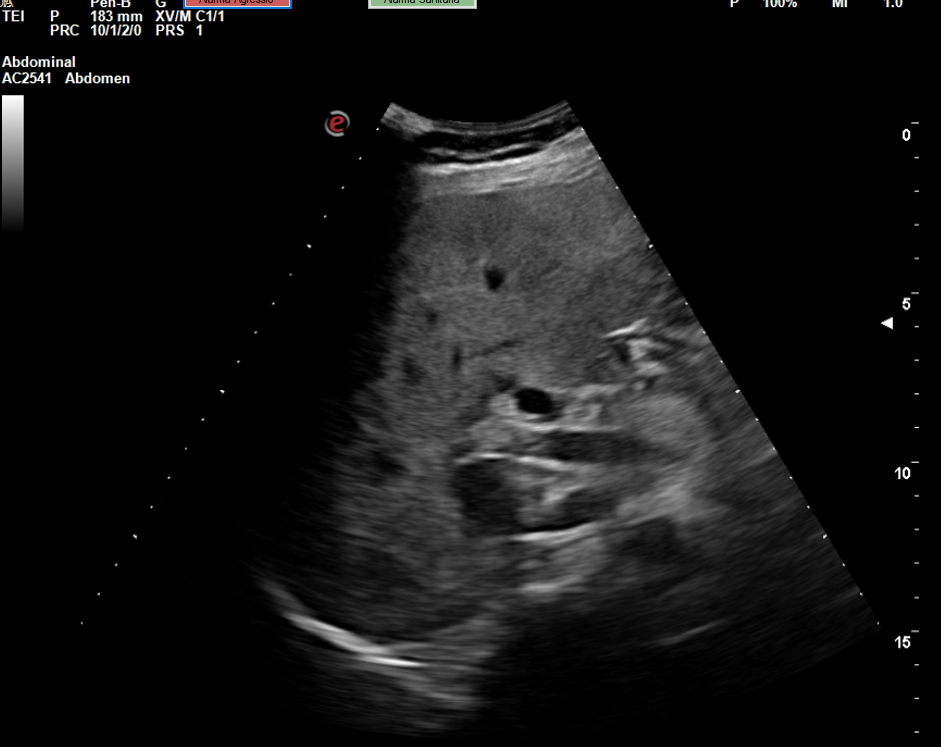

Se realiza la ecografía abdominal en el ambulatorio, donde se objetiva colelitiasis con el colédoco en el límite superior de la normalidad (4,4 mm), también presenta esteatosis hepática grado I. El resto de la ecografía no presenta hallazgos de interés.

Colelitiasis con colédoco en el límite de la normalidad.